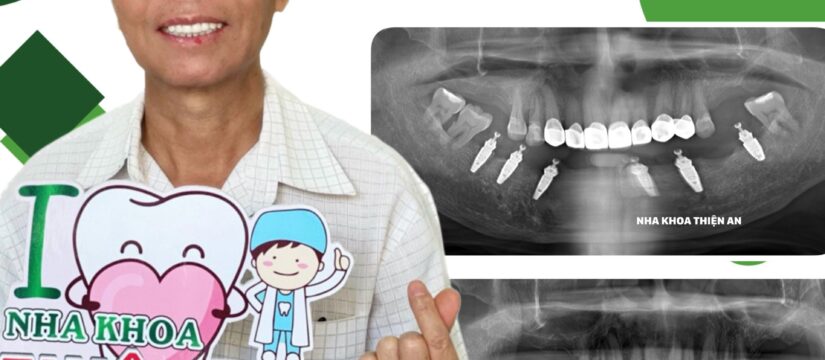

Cấy ghép implant toàn hàm 6 trụ implant Straumann xịn xò cho chú khách hàng dễ thương, có răng tạm tức thì ngay sau khi đặt trụ ạ

Tình trạng trước điều trị: các răng hàm dưới bị viêm nha chu nặng, lung lay muốn rớt ra ngoài, không còn khả năng điều trị và có chỉ định nhổ, phục hồi lại răng mất bằng implant toàn hàm All-on- 6 đảm bảo chức năng ăn nhai, bền vững với thời gian

Implanting 6 genuine Straumann implants for a cute customer, temporary teeth immediately after placing the posts

Condition before treatment: the lower teeth have severe periodontitis, are loose and want to fall out, can no longer be treated and are scheduled to be extracted and restore lost teeth with All-on-6 full-mouth implants. Ensure chewing function, sustainable over time